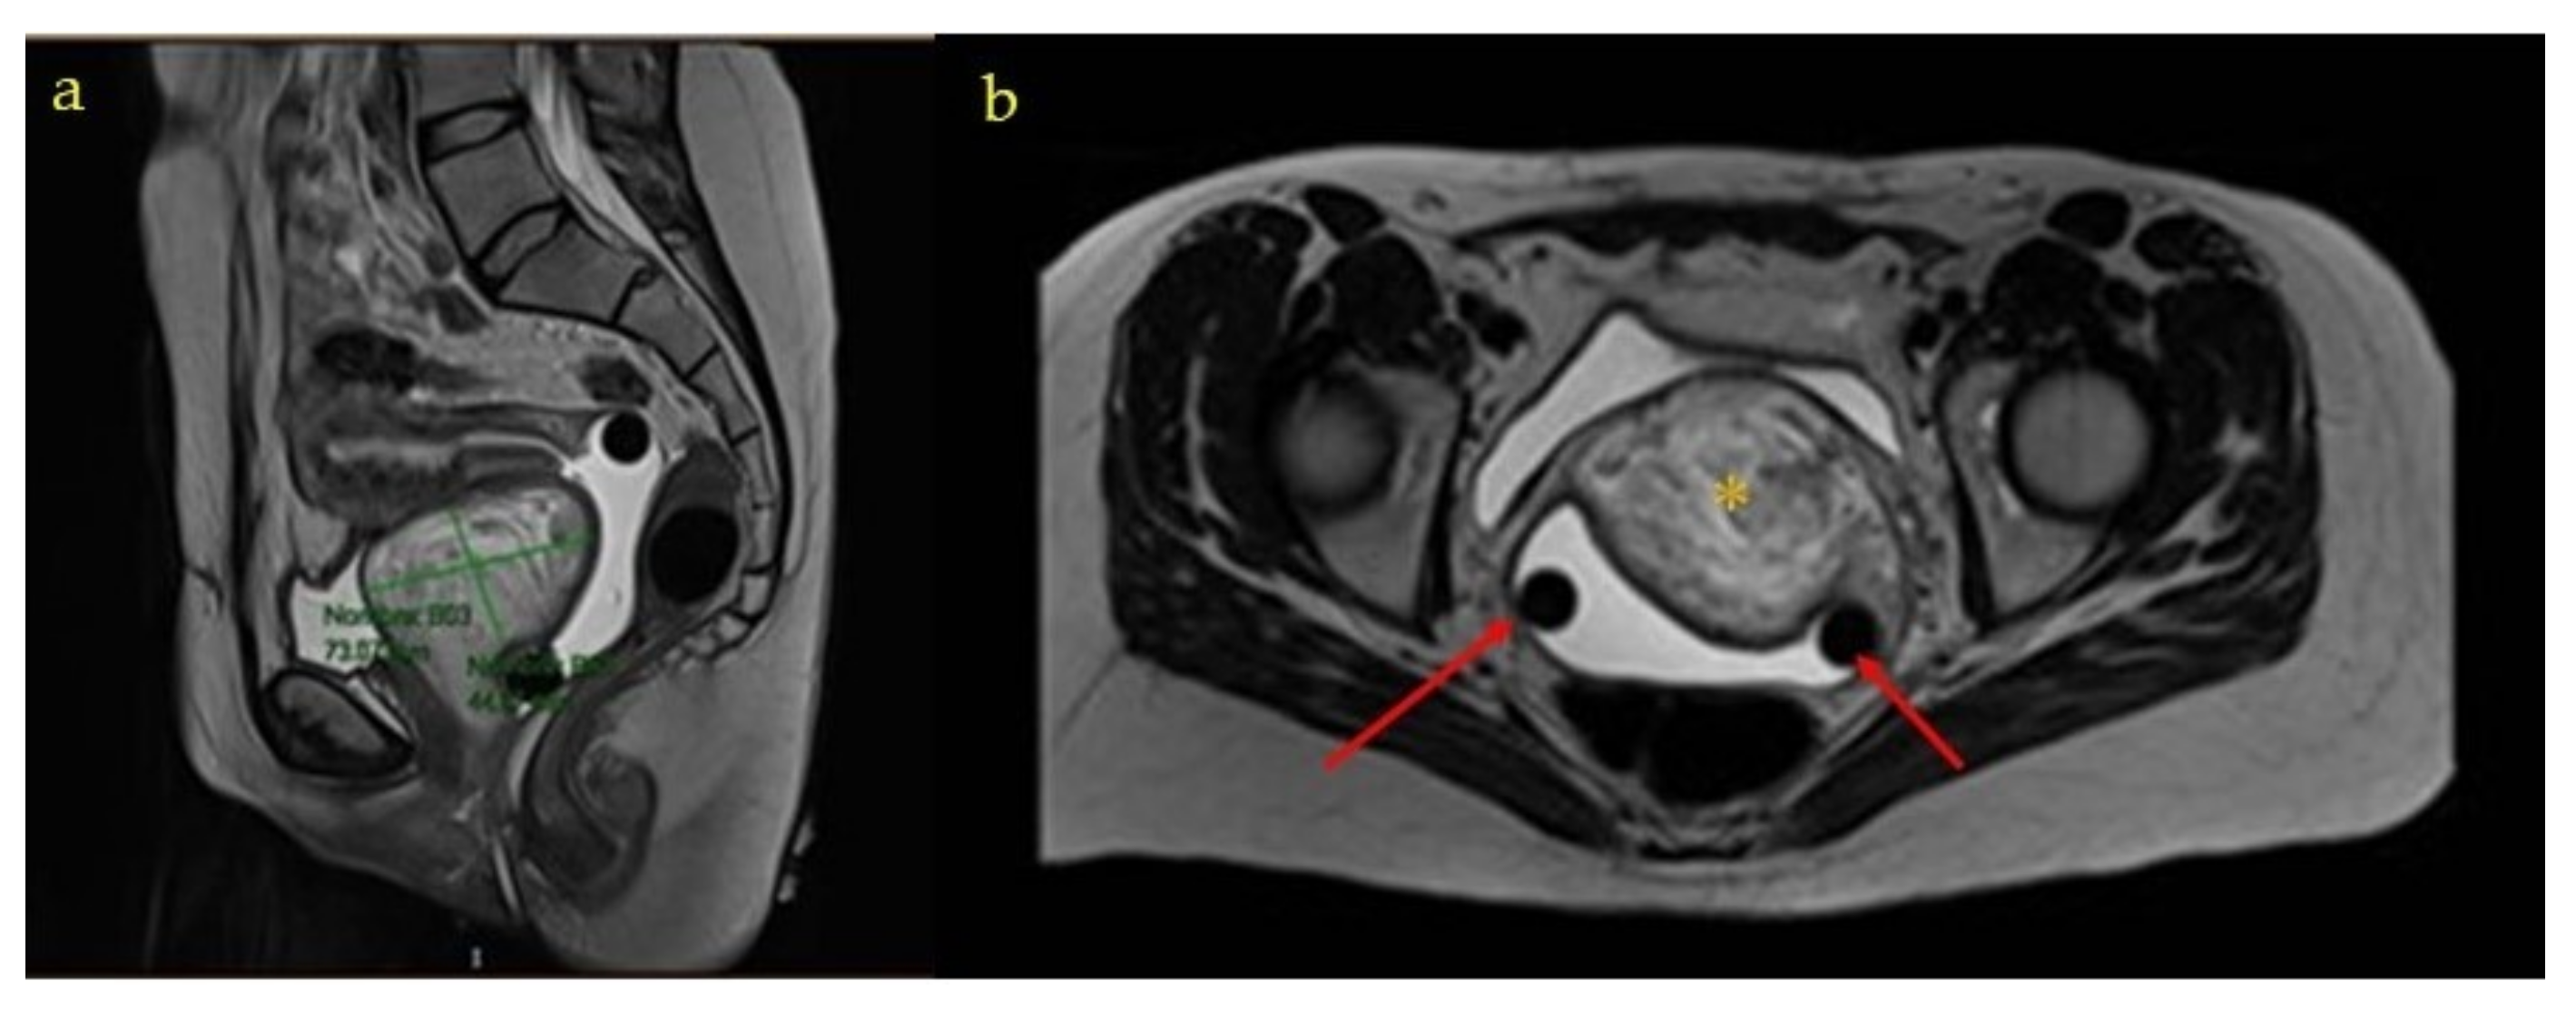

Subsequently, the patient was referred to the gynecology office after the puerperium, where a control transvaginal ultrasound was performed in which the previously described mass of heterogeneous appearance persisted in a difficult-to-delineate vesico-vaginal space. The internal genitalia were sonographically normal. A new pelvic MRI was requested, in which a complex, high-density 7 × 7 × 7.5 cm mass was observed, which did not seem to depend on any pelvic organ (Figure 5). The extension study was completed by computed tomography and was negative.

Figure 5. MRI images after pregnancy and before surgery: * Angiomyxoma (a) Axial section of the MRI. Yellow asterisk: angiomyxoma. Red arrows: gynecological pessary. (b) Sagital section of the MRI.